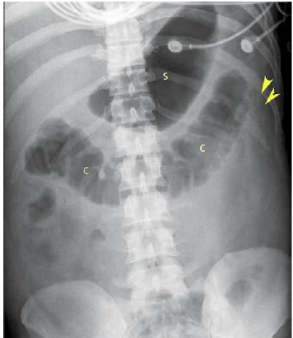

Jovem, masculino, 32 anos, é internado por episódios de vômitos de início há 24 horas, associado a dor abdominal refratária à analgésicos simples. Nega febre. Nega trauma recente. Nega sintomas urinários. Refere anorexia. Ao exame físico: regular estado geral, desidratado +++/4, corado, anictérico, afebril, taquicárdico. Ausculta pulmonar normal. Abdome com cicatriz prévia de laparotomia mediana por trauma (há 3 anos), distendido, ruídos abdominais muito reduzidos, doloroso em epigástrio e todo andar superior, mas sem sinais de peritonite. Realizou radiografia (abaixo) e foi submetido a ultrassonografia que visualizou vesícula biliar com parede de 3 mm, com cálculos em seu interior, múltiplos, todos com tamanho menor que 5 mm, e ducto colédoco com 4 mm. O pâncreas não foi visualizado por interposição gasosa. A principal hipótese diagnóstica e o tratamento mais adequado é: